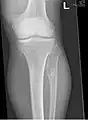

The diagnosis of HMO is based upon establishing an accurate correlation between the above-mentioned clinical features and the characteristic radiographic features. Family history can provide an important clue to the diagnosis. This is supplemented by testing for the two genes in which pathogenic variants are known to cause HMO namely EXT1 and EXT2. A combination of sequence analysis and deletion analysis of the entire coding regions of both EXT1 and EXT2 detects pathogenic variants in 70–95% of affected individuals.[3][4] The hallmark of radiographic diagnosis is the presence of osteochondromas at the metaphyseal ends of long bones in which the cortex and medulla of the osteochondroma represent a continuous extension of the host bone. This is readily demonstrable in radiographs of the knees.[3][1]

multiple osteochondromas around the knee